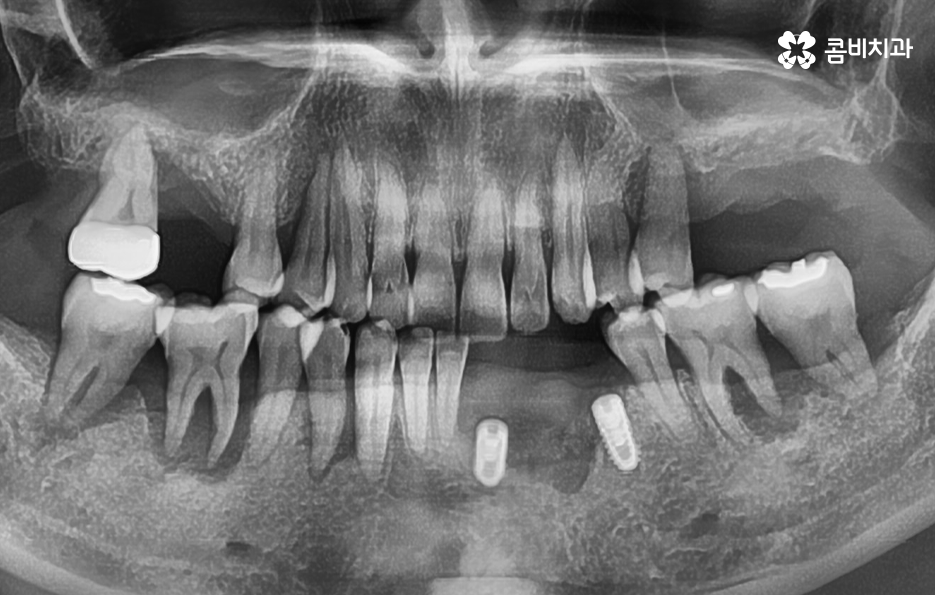

치아 옆면 충치는 치아와 치아 사이에 맞닿는 부분에 발생하기 때문에 최소 2개의 치아에서 발생되는 경우가 일반적이며 습관적인 부분이 원인이 되기 때문에 치과 치료가 늦어지면 여러 치아에서 동시에 발생되는 경우도 자주 볼 수 있기 때문에 치아 수명을 급격히 저하시키는 원인이 되고 있어요

치아 옆면 충치 뿐 아니라 잇몸이 내려앉는 문제 역시도 치아 사이 뿐 아니라 잇몸 속에 이물질이 쌓이고 쌓이다 보면 치석의 형태가 되고 치석 관리가 잘 안되어 입안에 세균이 증가하면 잇몸 염증 뿐 아니라 잇몸 퇴축으로 이어지기 때문에 치아의 사이 충치와 치주염은 중년 이후에 치아의 수명을 복합적으로 저하시키는 대표적 원인이 되고 있어요

종합하면 치아 사이에서 발생되는 충치와 잇몸이 내려앉는 문제는 서로 치아의 수명을 급격히 저하 시키는 시너지 효과가 있기 때문에 예방이 무척이나 중요하며 단순히 나이가 들어서 이러한 불편함이 있다고 생각하지 마시고 잇몸이 내려 앉거나 이 사이가 불편한 시림, 통증 등을 느낀다면 꼭 원인 파악을 제때 하시길 권하고 있어요